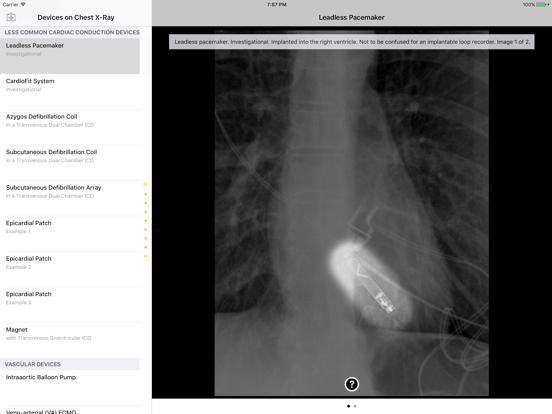

Introducing the Atlas of Medical Devices on Chest Radiography – one of the largest and most comprehensive collections of medical devices on chest radiography in existence. This app is an outstanding resource for physicians, physicians-in-training, and many healthcare providers who encounter medical devices on chest x-rays in daily practice. Review and explore the appearances of common and uncommon medical devices, organized by category. Search for a medical device in seconds using this app's lightning quick search feature.

· Countless images, organized into the following categories: Common Cardiac Conduction Devices, Less Common Cardiac Conduction Devices, Vascular Devices, Airway Devices, Enteric Devices, Neurological Devices, Musculoskeletal Devices, and Miscellanenous Devices.

· Tap the caption icon to read more about the device and to see it highlighted on the chest radiograph.